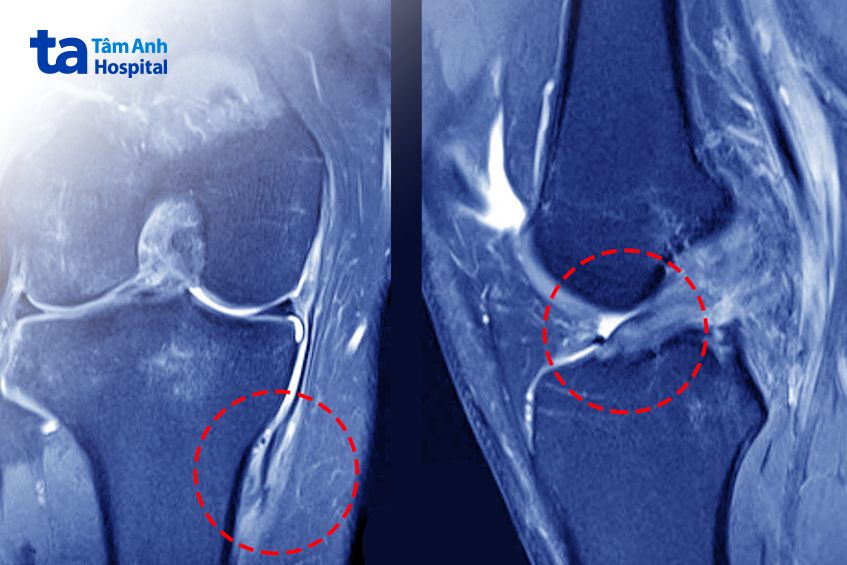

ThS.BS Vũ Trung Hiếu, Khoa Chấn thương Chỉnh hình, khám lâm sàng nghi ngờ bệnh nhân còn tổn thương khác chưa được chẩn đoán. Kiểm tra bằng nghiệm pháp ép vẹo ngoài khớp gối (Valgus) cho kết quả dương tính ở khoảng gấp 30 độ, đặc trưng của tình trạng đứt dây chằng bên trong (MCL). Hiệp được chụp lại cổng hưởng từ MRI, xác nhận dây chằng bên trong gối phải đứt tại điểm bám xương chày, kèm đứt dây chằng chéo trước, rách sụn chêm ngoài.

Tuy nhiên, Hiệp bị đứt dây chằng bên trong tại điểm bám xương chày, là vị trí khó liền, kèm đứt dây chằng chéo trước. Nếu chỉ phẫu thuật tái tạo dây chằng chéo trước, không phát hiện tổn thương dây chằng bên trong hoặc chỉ điều trị bảo tổn dây chằng này, hậu phẫu sẽ làm tăng áp lực, nguy cơ lỏng mảnh ghép tái tạo trở lại, phải phẫu thuật tái tạo lần hai với rủi ro lớn hơn, khả năng phục hồi thấp hơn, bác sĩ Hiếu cho biết.